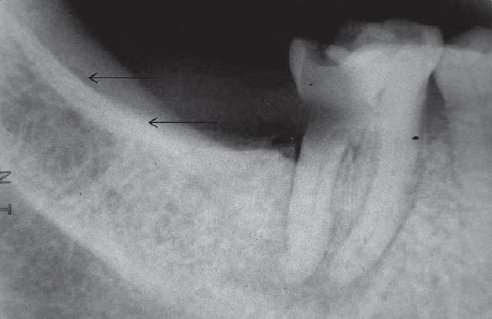

62. What is the anatomical structure indicated by arrow in this radiograph?

21 / 40